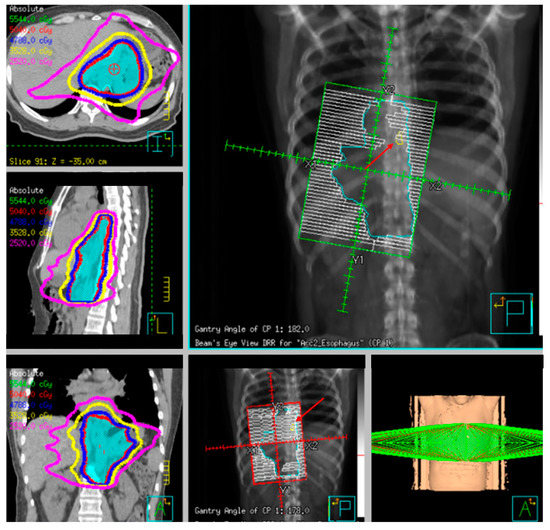

3.3. Multimodality Therapy for Locally Advanced Esophageal Cancer

3.6. Definitive Radiation and Chemoradiation

6. Chemotherapy and Radiation